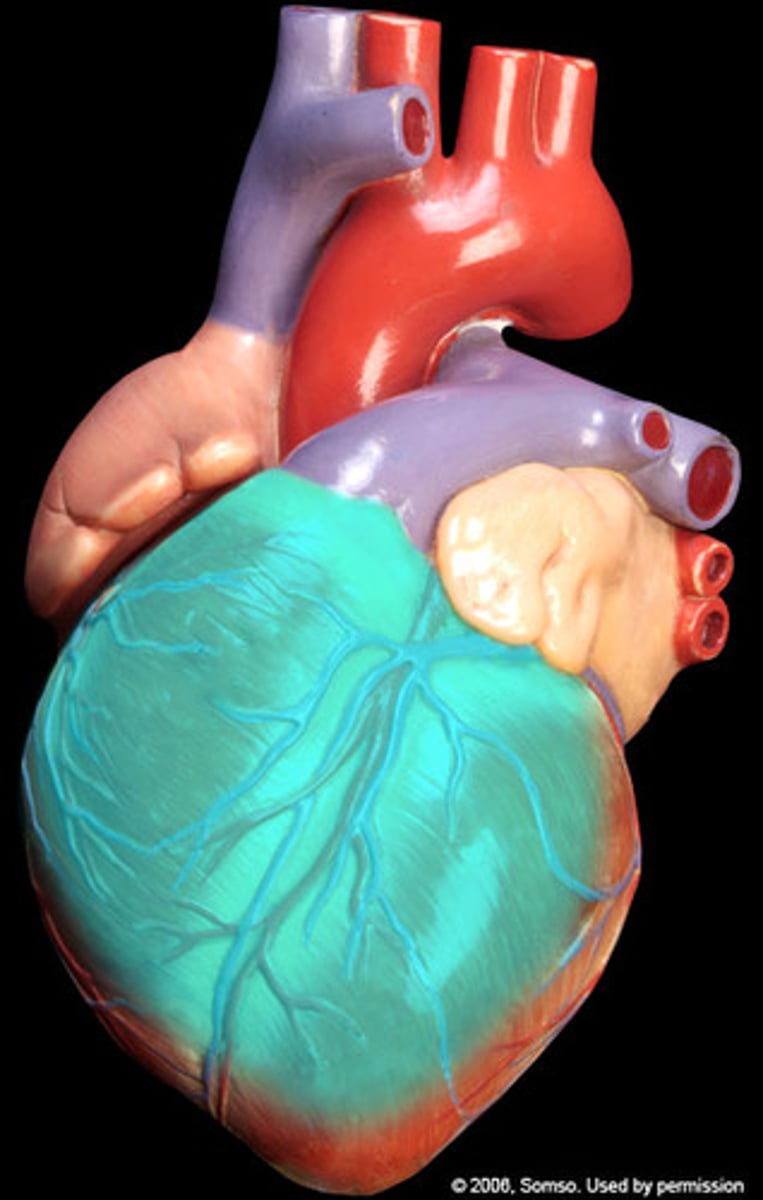

Anterior Surface of the heart

"region", front side of the heart